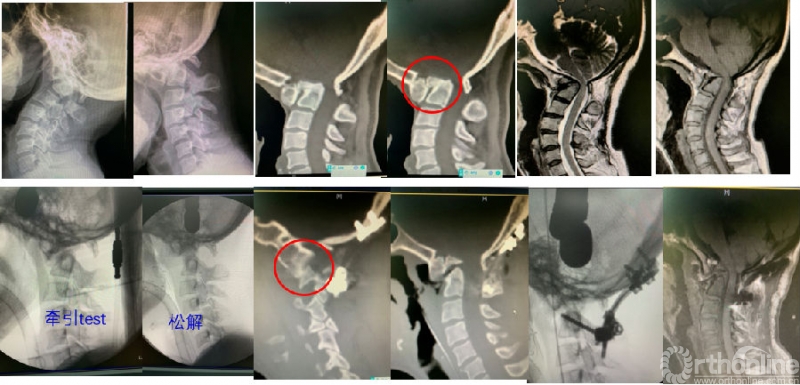

北医三院诊治策略指出,寰枢椎脱位的分类需要依据三个手段:动力位X线片、重建CT及全麻后牵引试验。可分为:不稳定、可复性脱位、难复性脱位及骨性脱位,参考图1。

图1:寰枢椎脱位的分类。术前动力位X线片显示可以复位的诊断为type I(不稳定);术前CT显示骨性融合的诊断为type IV(骨性脱位);术前动力位显示虽有微动但无法复位的,应用术中全麻后牵引试验:麻醉牵引后复位的是type II(可复性脱位)、无法复位的诊断type III(难复性)。